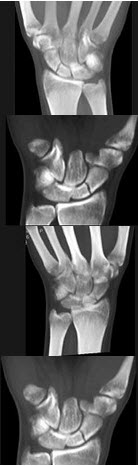

105、单项选择题

女,45岁,结合图像,最可能的诊断是()

A.类风湿关节炎

B.痛风

C.假痛风

D.牛皮癣性关节炎

E.神经性关节病

点击查看答案